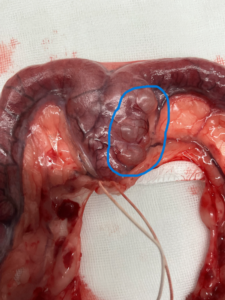

下に同じ犬種の卵巣・子宮の写真を添付します。

※拡大写真の青色の〇で囲っている箇所が嚢胞状の病変になります。